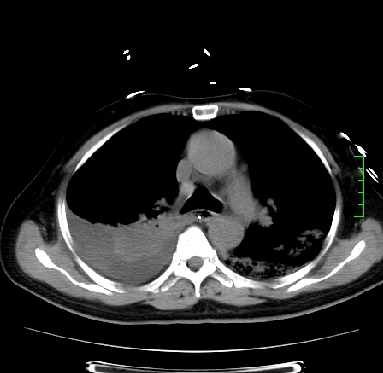

icu病人,几天都没明确诊断。m,76y,咳嗽、咳痰1周,伴气促,右胸痛入院,pe:t38.3c p135 r25 bp135/85。双肺可闻及大量湿罗音,心、腹未见明显异常。诊断:1心衰?2肺部感染?3冠心病?

11号ct

双肺感染性病变,下叶膨胀不全,胸水,左室大。

1)两肺感染性病变(右肺下叶肺脓肿可能)。2)双侧胸腔积液,以右侧为甚。

ards,肺感染性病变,右下叶实变,双侧胸腔积液,右侧为著,叶间胸膜积液,右上肺陈旧性tb纤维灶,左室大。